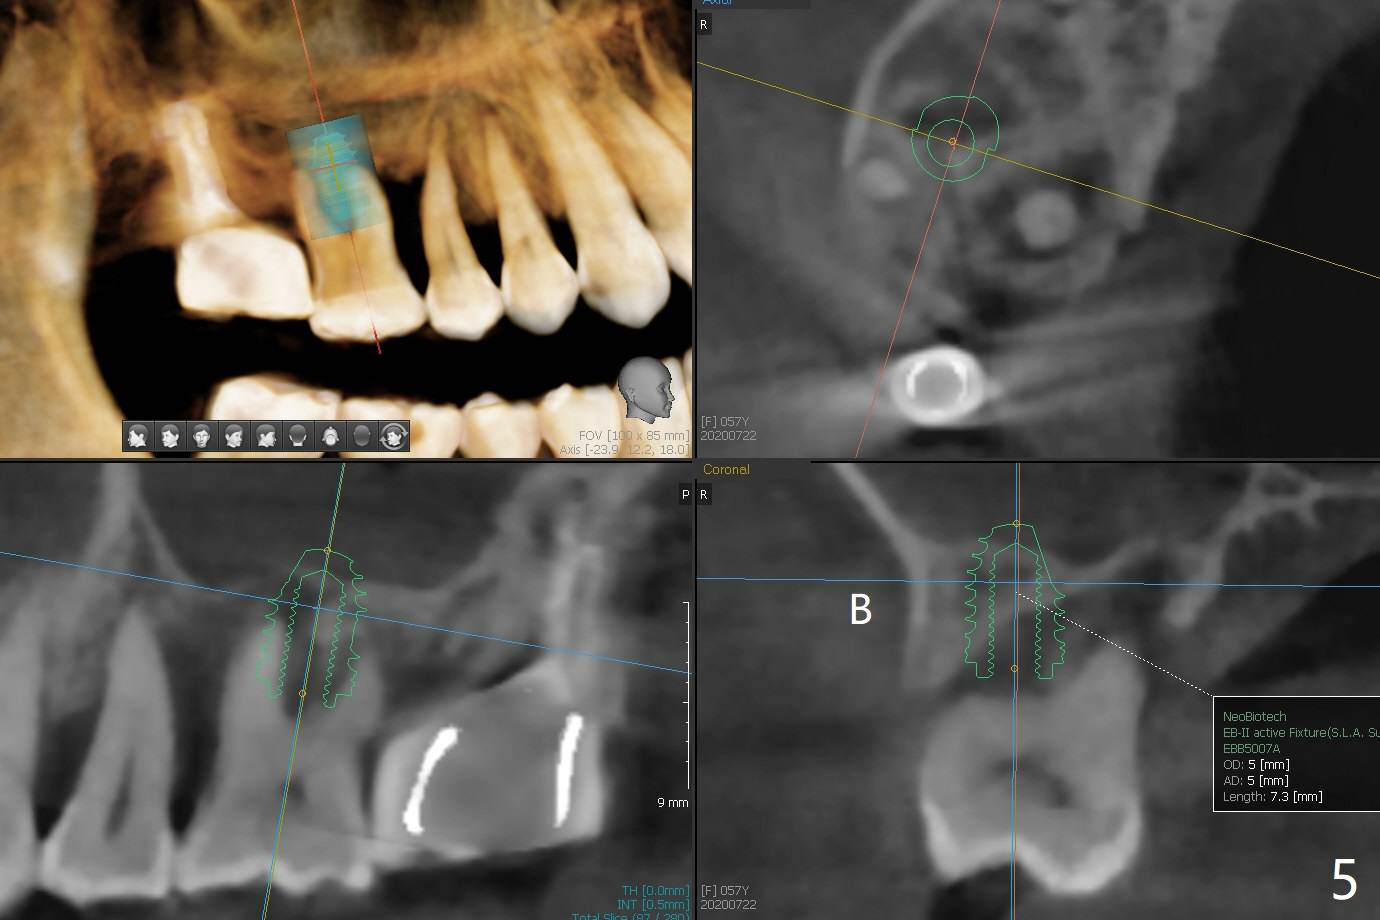

57岁女严重牙周炎,主诉右上磨牙食物堵塞(图一:圆圈)。第一磨牙骨质吸收,松动,需要拔除,尽管骨壁2-3毫米(图二),使用导航应该能取得5乘7.3毫米植体(图三绿色)初步稳定性。上颌窦膜厚,提升术不容易破裂,使用PRF膜预防及修补。由于近中骨质缺损严重(图三 *),植体可以再提高些(箭头),利用粘性骨做提升以及骨质缺损充填,似乎颊侧骨质多些(图五),植体可以小些,万一不行,就做提升和植骨。左上磨牙区骨壁更薄(图四,约1毫米),外提升术之后再种植。